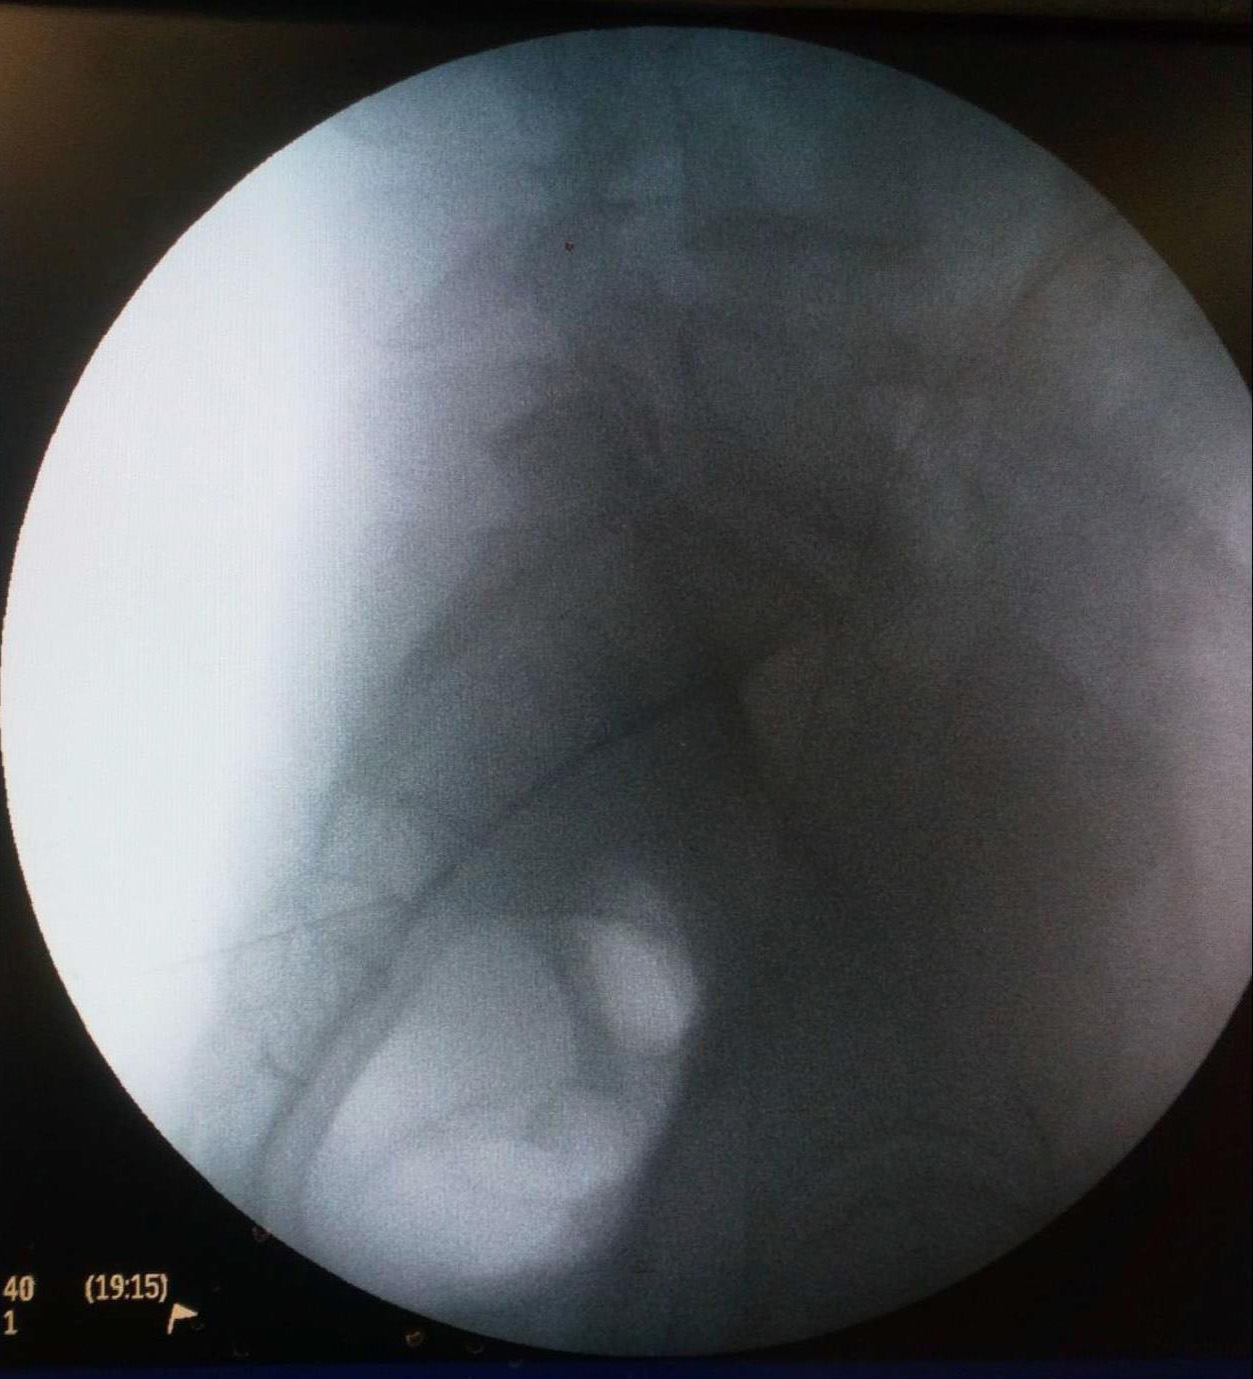

Ασθενής με 2 δισκοκήλες

Aσθενής 35 ετών με έντονο άλγος οσφύος από 4μήνου και αντανάκλαση στο κάτω άκρο λόγω 2 δισκοκηλών σε 2 επίπεδα. Με τοπική αναισθησία τοποθέτηση 2 βελόνων στα σημεία πίεσης των νεύρων. Έλεγχος σωστής τοποθέτησης με χρήση σκιαστικού και εισαγωγή μείγματος αναλγητικών. Άμεση ανακούφιση με αποτέλεσμα που διατηρείται 6 μήνες μετά.